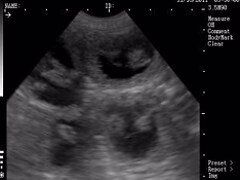

We are trained, qualified and certified in Canine ultrasound scanning and we want to offer the best service possible. We usually carry out the first scan on day 30, this one is purely to confirm that your bitch is pregnant, we can usually offer an estimate of numbers at this time but it is only an estimate as reabsorption can still take place up to day 44. A second scan can be done at your choice but it depends on what it is for, we always say for a peace of mind scan book in for around day 40-45 but this is up to you.

Here is a short video clip from a client’s scan of their Bulldog on day 49 and as you can see, the heartbeats are clearly visible at this stage

- Someone trained in Canine ultrasound scanning should be able to assure you that the unborn puppies are healthy. This is done by not only looking for gestation sacs but by confirming movement and more importantly, heartbeats. Scanning prior to 40 days makes this extremely difficult as seeing a heartbeat at this stage would be almost impossible on most portable scanning machines.

- If you want peace of mind that the pregnancy is all progressing as it should after you’ve had your confirmation scan then wait until around day 40-45 as the puppies will be a lot more developed and this is when the heart beats are usually more visible. This not only gives you better images, but also assures you that the pregnancy is progressing normally.